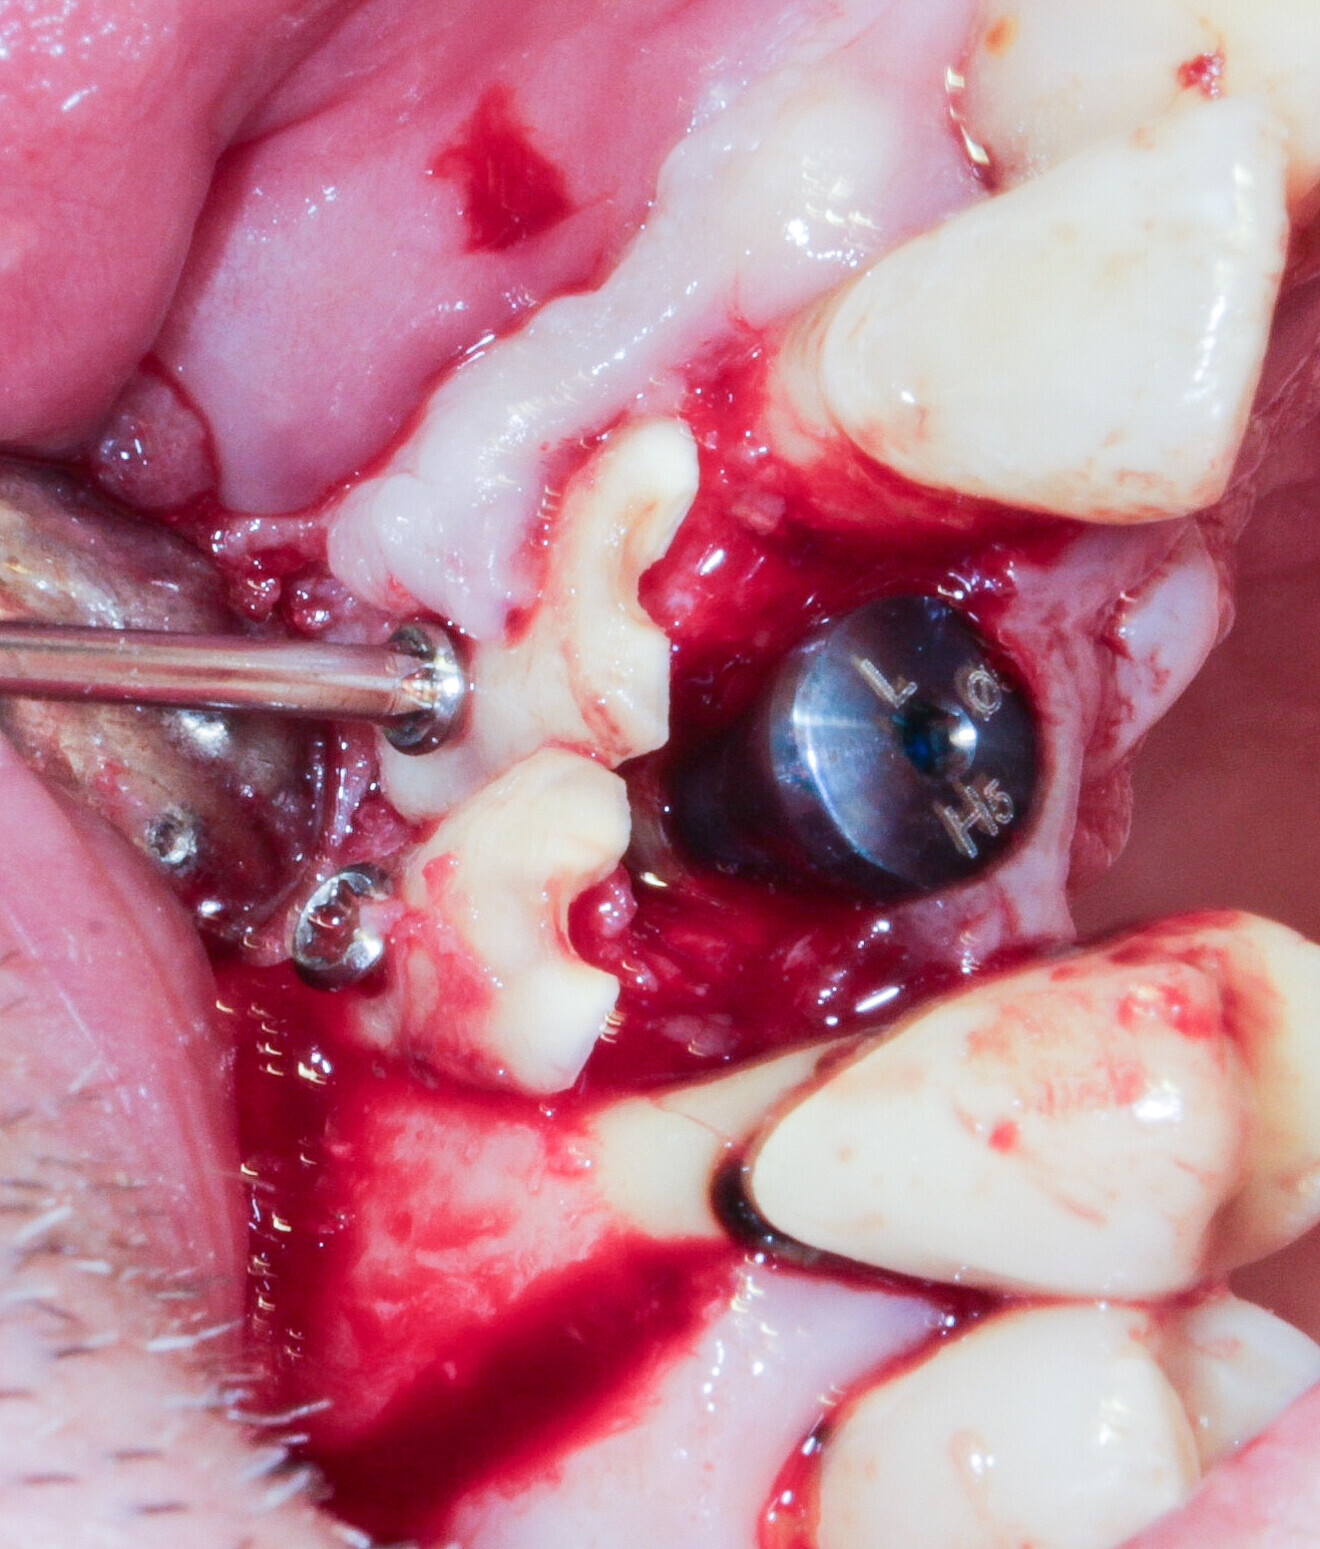

Fig. 16: Preparation of the root and fixation with an osteosynthesis screw to replace the lost wall.

A 55-year-old patient with a radicular fracture at tooth #13 under a crown and a fistula opposite was treated (Fig. 15). The plan was to treat this patient with simultaneous extraction, implantation and aesthetic restoration. Unfortunately, as sometimes happens and despite the precautions taken, a large part of the vestibular wall of the alveolus was extracted with the root, creating a significant bone defect. A full-thickness flap was elevated and the implant placed. The root was prepared and fixated with an osteosynthesis screw to replace the lost wall (Fig. 16). The space between the root and the implant was filled with a hydroxyapatite-based biomaterial (Fig. 17). This bone reconstruction was combined with a connective graft. The flap was stretched and sutured with a #5/0 resorbable braided thread (Fig. 18). An impression was taken and a temporary screw-retained prosthesis was made during the day by the laboratory and fitted the same evening. The sutures were removed on the tenth day. The temporary prosthesis was removed after two months to check that the implant had been successfully integrated into the bone. The osteosynthesis screw was visible under the gingiva and was removed after six months (Figs. 19 & 20). A CBCT assessment was performed at the same time. The radicular graft had ankylosed perfectly and the ridge regenerated ad integrum. The definitive prosthesis was fitted by our colleague (Fig. 21).